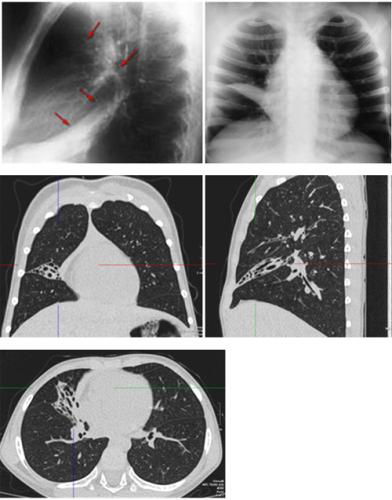

Помимо опроса и объективного осмотра, включающего перкуссию и аускультацию грудной клетки, проводят рентгенологическое исследование в двух положениях тела (в 2-х проекциях). Это основной метод обнаружения ателектазов легких.

На рентгеновских снимках выявляют следующие признаки, указывающие на спадение легочной ткани:

Однородное затемнение в области поражения. Размеры тени зависят от вида ателектаза: при долевом выявляется обширное затемнение, при сегментарном — в виде клина или треугольника, расположенного вершиной к корню легкого, дольковые ателектазы множественные и похожи на очаговую пневмонию. Дистензионный ателектаз расположен низко, около диафрагмы, имеет небольшие размеры и вид поперечных полос или темных дисков. Смещение органов: при компрессионном ателектазе смещение наблюдается в здоровую сторону, так как на стороне поражения давление больше, при обтурационном, наоборот – смещение будет в сторону ателектаза, так как на стороне поражения нарастает притягивающее отрицательное давление. Подъем купола диафрагмы – это видно по расположению печени.

Помимо всего перечисленного выше, рентгеноскопия, то есть исследование «вживую», позволяет увидеть куда смещаются органы в зависимости от фазы дыхания, кашля. Это является дополнительным признаком ателектаза, помогающим выявить тип болезни.

Предварительным, рентгенологическим диагнозом является «синдром правой доли», при котором выявляется затемнение площади средней доли правого легкого.

Частое возникновение ателектаза правого легкого связано с анатомическими особенностями правого среднедолевого бронха: он узкий и длинный, поэтому часто происходит его перекрытие при патологическом процессе.

Если диагноз непонятен, рентгенологическое обследование дополняют компьютерной томографией. При перекрытии просвета бронхов выполняют бронхоскопию – осмотр по ходу бронхов с помощью зонда с камерой, который вводят в дыхательные пути.

При исследовании обнаруживают причину блока и уровень его расположения.

Длительные ателектазы требуют проведения контрастных методов исследования: бронхографии и ангиопульмонографии. Исследование дает информацию о глубине поражения левого и правого легкого, выявляет деформацию бронхов, а также оценивает ход сосудов.